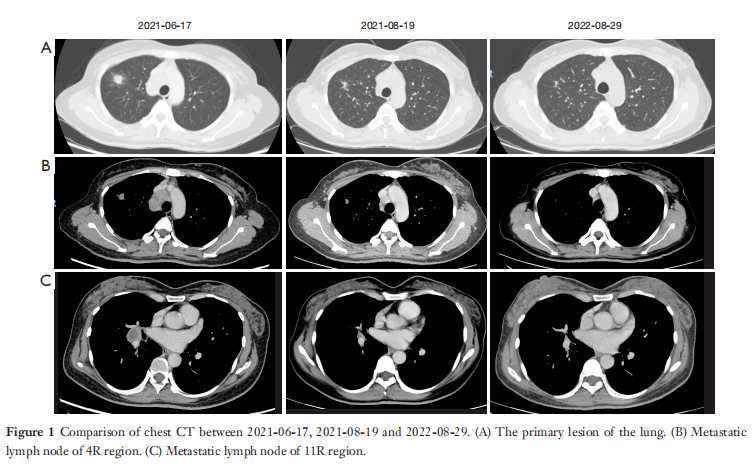

該患者於2021年6月16日住院治療。在 2021年6月17日,胸部CT顯示右肺上葉前段有一個19×16×30mm的結節狀陰影,鄰近胸膜受累,並在右側肺門和縱隔的2R和4R / L(右/左)處觀察到多個腫大的淋巴結。較大淋巴結的短直徑約為21mm。上腔靜脈腔因淋巴結推擠而變窄,並考慮淋巴結轉移(圖1)。2021年6月21日,進行了超聲支氣管鏡檢查,在縱膈的4R、4L和縱膈的7個區域、右肺門(10R)和右小葉間(11R)發現多個低回聲腫塊。病變的最大短直徑約為20.4×30.6mm,在4R區(圖2)。

圖1 2021-06-17、2021-08-19和2022-08-29的胸部CT對比。(A)肺部的原發病變。(B)4R區的轉移性淋巴結。(C) 11R區的轉移性淋巴結。

經過胸部腫瘤外科醫生的評估,醫生建議術前進行2-4個周期的新輔助化療,並進行綜合評估以確定是否可以進行手術切除。患者因個人原因拒絕化療,2021年7月18日,根據中國臨床腫瘤學會(CSCO)2020年指南,患者開始使用ALK酪氨酸激酶抑制劑阿來替尼治療,劑量為600 mg,每日兩次。經阿來替尼治療1個月後,肺腫瘤大小由19×16×30縮小至13×11×14 mm,最大肺門及縱隔淋巴結由21 mm縮小至14 mm,上腔靜脈壓力也有所下降(圖1)。根據實體瘤療效評估標準(RECIST1.1),該腫瘤反應判定為部分緩解(PR)。隨後,患者每2個月接受一次檢查,腫瘤繼續縮小。2022年6月24日,患者做了正電子發射斷層掃描(PET)-CT,仍有腫瘤殘留,腫瘤大小與2022年4月28日相同。2022年8月29日,也就是阿來替尼治療12個月後,肺部腫瘤大小已縮小到9×6 mm(與2022年4月28日胸部CT相比),肺門和縱隔淋巴結短直徑為8 mm,癌胚抗原(CEA)水平繼續下降(圖4)。